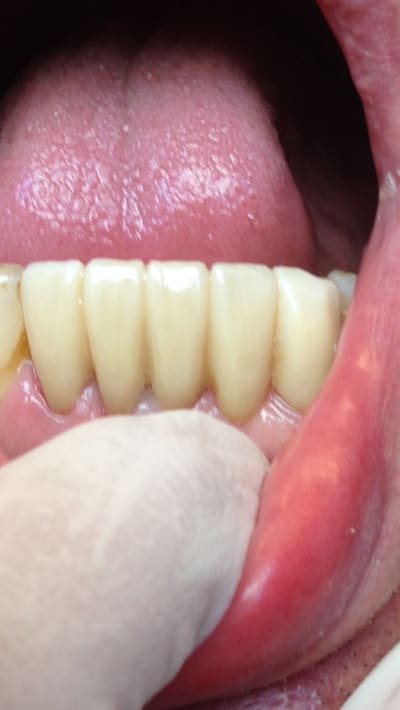

Petite Chinoiserie de 33 à 42 de derrière les fagots .

Ah aujourd'hui c'est latex... ça change! Enfin le doigt est tout de même devant :-))

C'est selon les préférences de chacun. Certains préfèrent le doigt devant , d'autres derrière .

Et puis Le but c'est de montrer aussi par la même occasion la qualité des gants chinois 😊